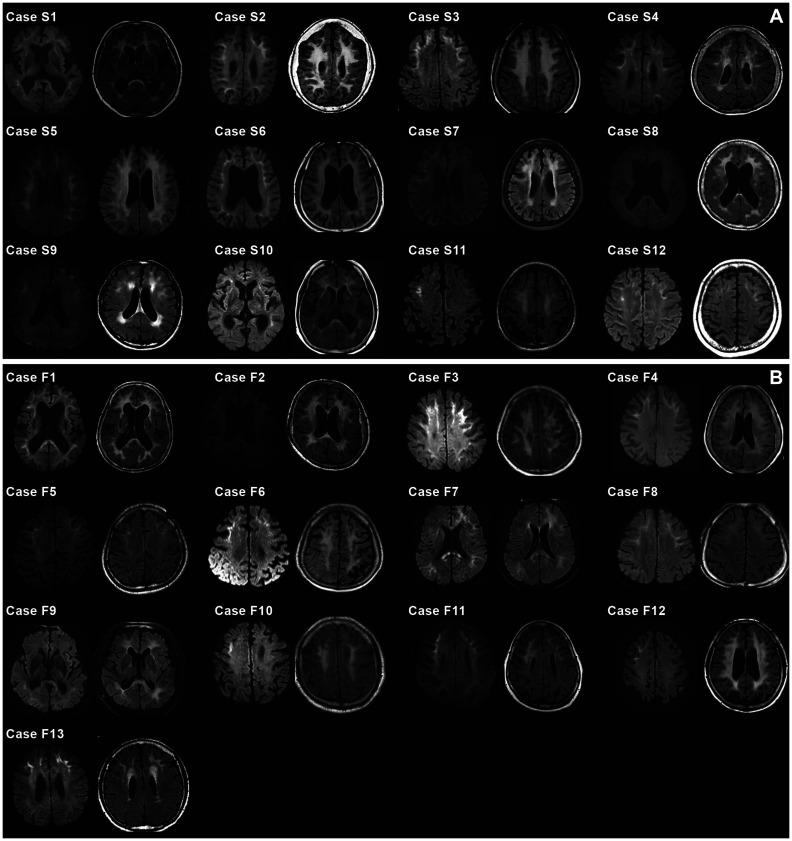

Results: The 25 reviewed NIID patients comprised 12 (48.0%) sporadic and 13 (52.0%) familial cases, with the latter showing a significantly higher proportion of males (p=0.027). The patients were classified into three subtypes based on the prominent symptoms: NIID-Episodic (44.0%), NIID-EPS (extrapyramidal symptoms) (36.0%), and NIID-Dementia (20.0%). Most patients (92.0%) also exhibited other symptoms, including peripheral neuropathy (60.0%), bladder dysfunction (48.0%), or ophthalmic problems (56.0%). Hyperintensities along the corticomedullary junctions in diffusion-weighted imaging and extensive white-matter hyperintensities in fluid-attenuated inversion-recovery imaging were observed in 96.0% and 100% of the patients, respectively. GGC repeat expansion in NOTCH2NLC was identified in 6 sporadic and 10 familial cases. The number of GGC repeats was not correlated with the onset age or clinical symptoms.